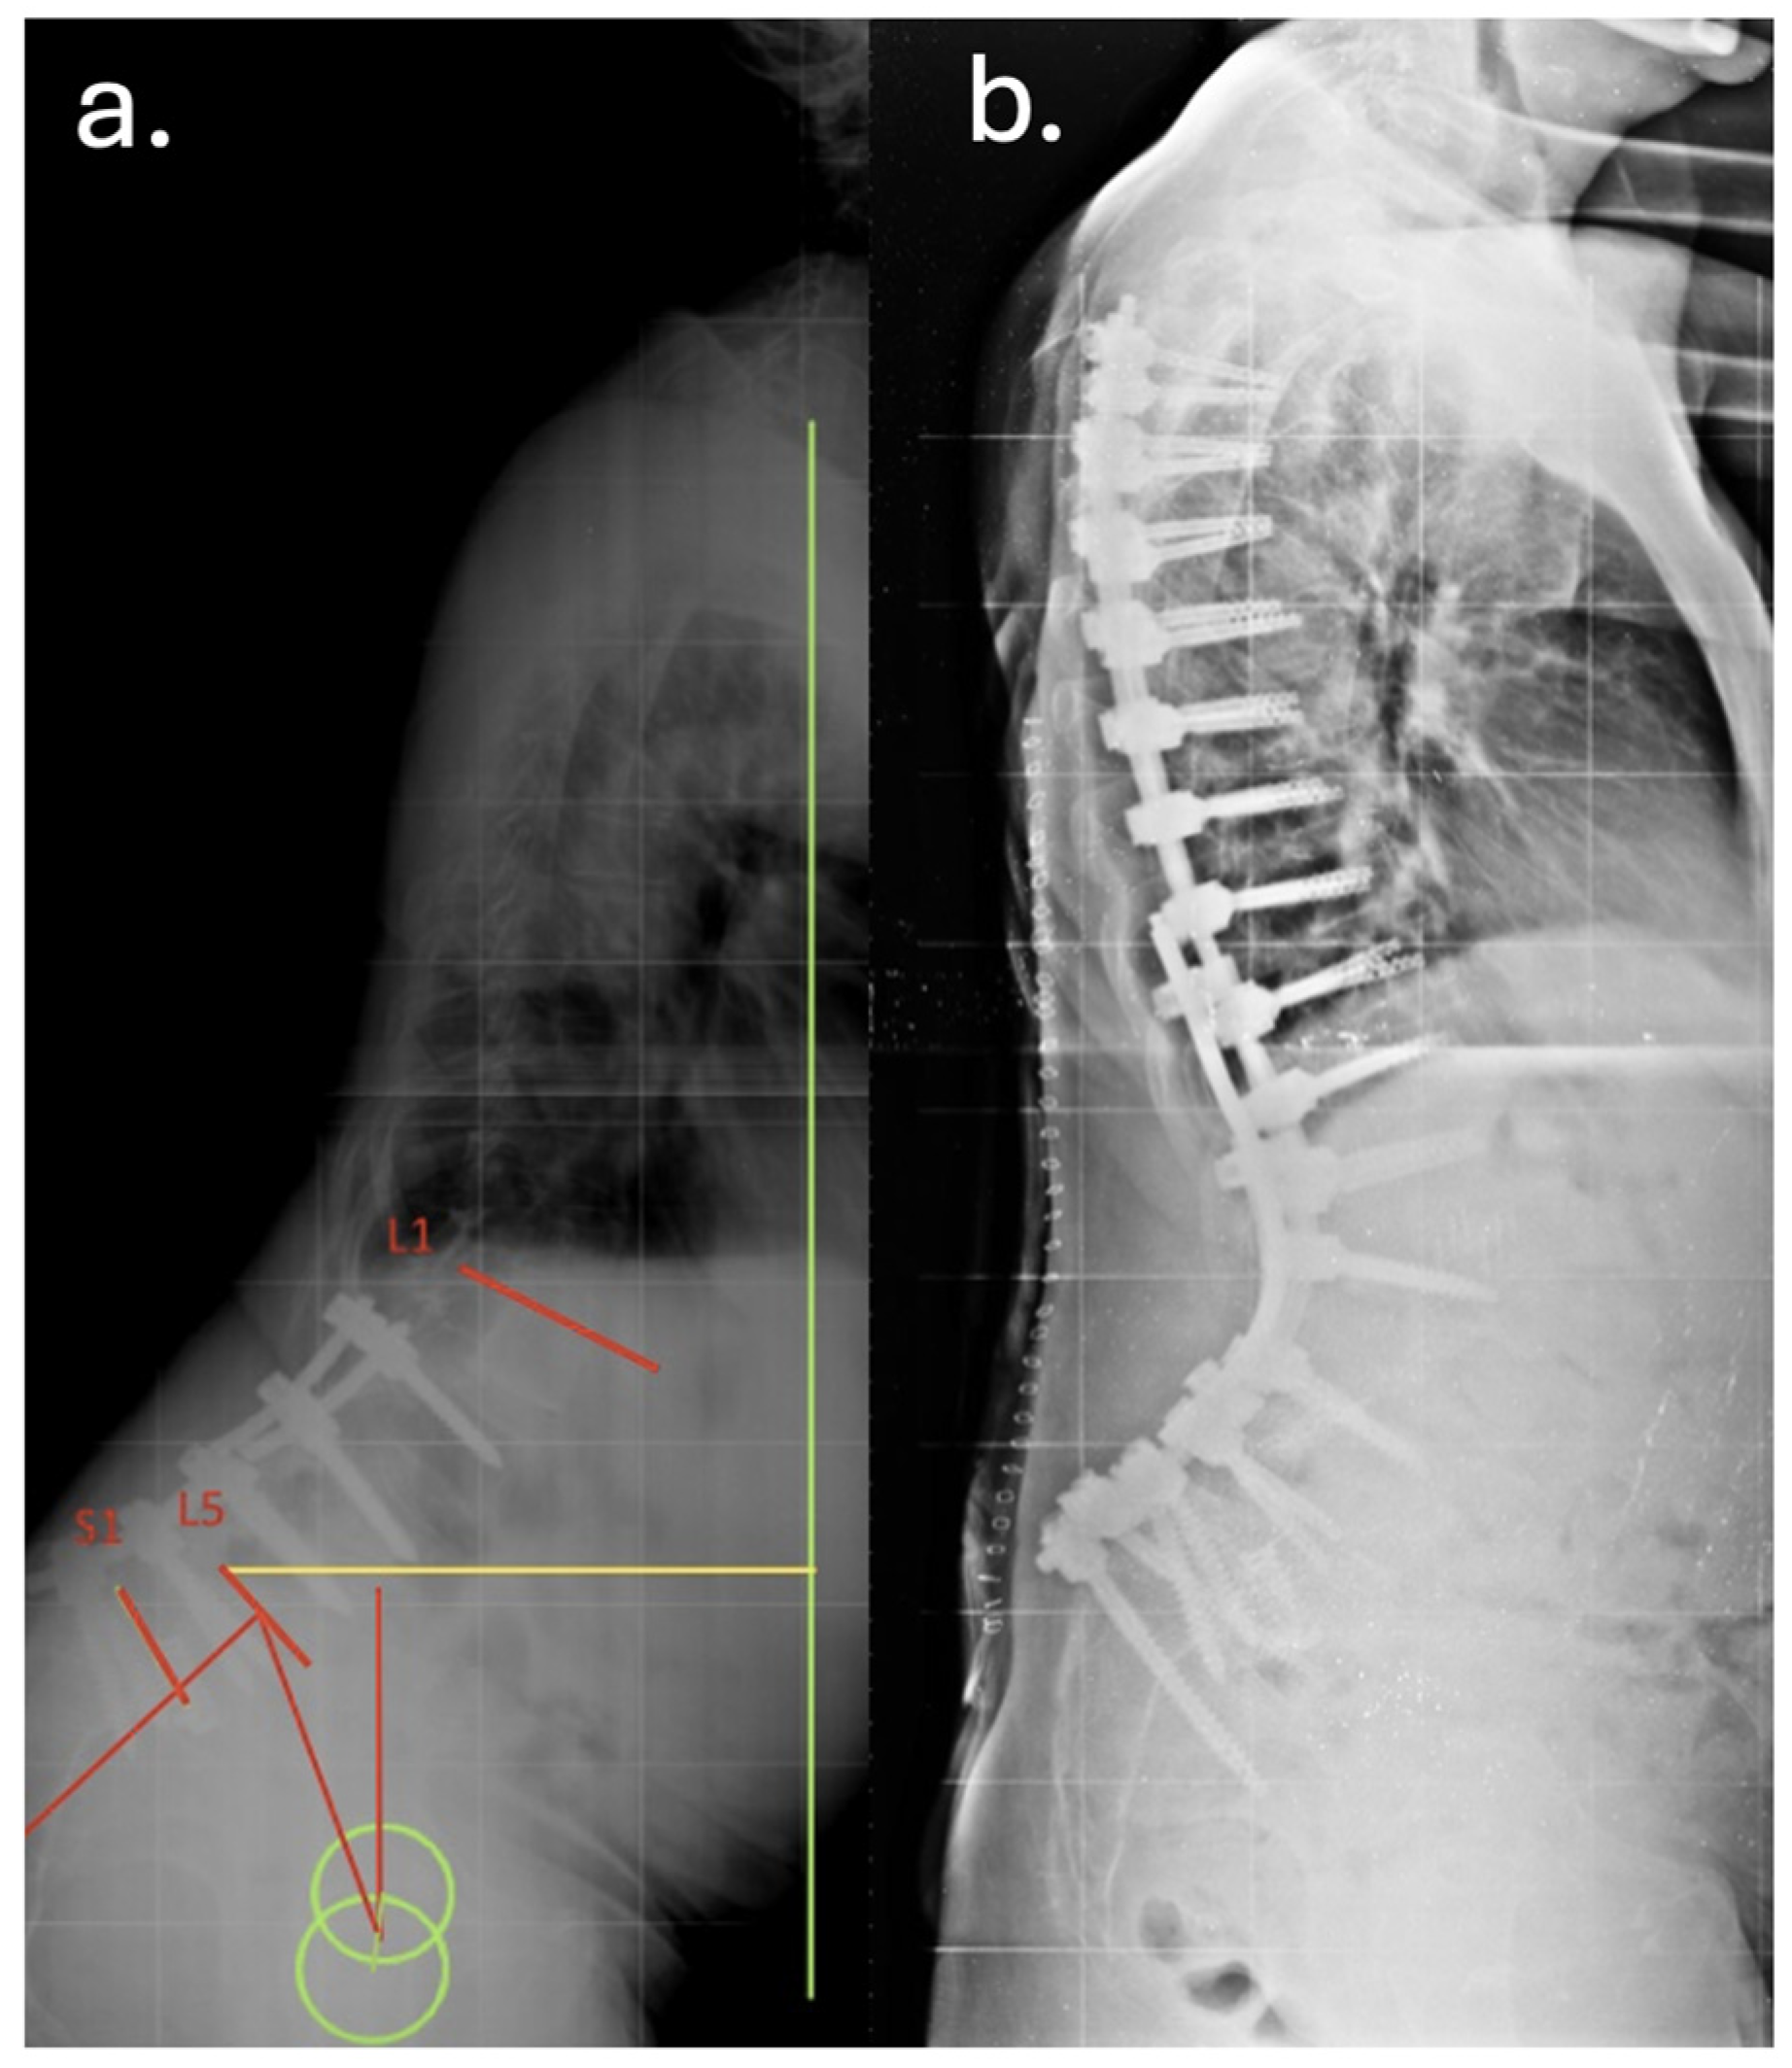

Despite temporary clinical improvement, progressive sagittal imbalance and worsening pain prompted a fourth surgery in June 2016, she underwent a major posterior revision: all prior instrumentation was removed and replaced with new rods and screws extending from T7 to the pelvis, including bilateral iliac fixation as showed in Figure 2 and Figure 3. Postoperatively, the patient developed high-grade fever and was diagnosed with a urinary tract infection due to Acinetobacter baumannii XDR. She was treated with multiple antibiotic courses, including teicoplanin, tigecycline, and colistin.

Figure 2. Preoperative (a) and postoperative (b) lateral radiographs documenting the first revision surgery with extension of the arthrodesis from T2 to the ilium. The images show restoration of sagittal alignment, with correction of the sagittal vertical axis (SVA) and improvement of lumbar lordosis.